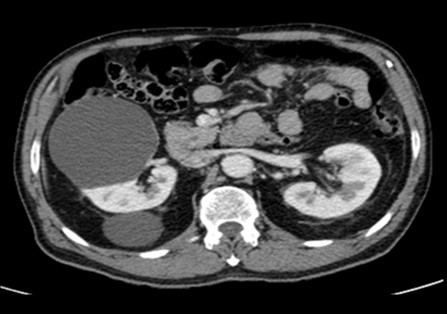

La Categoría I define la lesión como densidad agua (0-20 UH), sin septos o calcificaciones, ausencia de polos sólidos y sin realce a la administración de medio de contraste yodado IV.(19, 20) Su clasificación sería de quiste simple benigno y no requeriría ningún tipo de evaluación posterior. Son lesiones asintomáticas que rara vez requieren tratamiento. No es necesario realizar controles posteriores (Anexos 3 y 4).

La Categoría II define una lesión con septos finos lisos (< 1mm), calcificaciones lineales continuas o discontinuas o lesiones densas homogéneas en la pared o tabique pero que no experimentan realce a la administración de medios de contraste yodado IV en TC o paramagnéticos en RMI. Su clasificación es de lesión benigna (proteáceos, hemorrágicos, infecciosos).(19, 20) Estos quistes son hiperdensos (40-90 UH < 3cm), mínimamente complicados y no precisan cirugía, deben ser controlados (Anexos 5 y 6).

La Categoría IIF exhibe múltiples septos finos en su interior, realce evidente en paredes o septos, mínimo grado de engrosamiento de la pared, calcificación grosera o nodular, lesiones intra renales densas sin realce o con realce de septos o pared, siendo este realce no medible en las lesiones descubiertas con incremento de la densidad radiológica cuando se comparan las imágenes sin y con contraste yodado IV. Se consideran masas quísticas moderadamente complicadas y precisan seguimiento con controles cada seis meses.(19, 20) No requieren tratamiento quirúrgico inmediato y el riesgo de evolucionar a quistes malignos es del 5%, quistes con aspecto hiperdenso > 3 cm (Anexos 7 y 8).

La Categoría III muestra engrosamientos lisos o irregulares de la pared o de los septos intra quísticos y existencia de realce medible en TC y RMI. Se consideran masas indeterminadas y precisan de primera instancia cirugía, nefrectomía parcial o ablación por radiofrecuencia, salvo contraindicaciones clínicas.(19, 21) Aproximadamente el 40%-60% son lesiones malignas (carcinomas renal quístico), siendo el restante benignas, que incluyen quistes hemorrágicos, infectados crónicos o calcificaciones parietales, nefrona quístico multiloculado, quistes multilobulados, quistes con tabiques complejos, etc. (Anexos 9 y 10).

La Categoría IV presenta captación de un componente sólido intra quístico, muestra realces nodulares fuera de la pared y de los septos interpuestos en el área quística compleja, calcificaciones gruesas, vascularizadas con un importante realce con contraste yodado IV. En realidad, son lesiones malignas con componente quístico. Se trata de neoplasias quísticas, y precisan cirugía y estadificación.(19, 21) (Anexos 11 y 12).

- Bosniak I: el 80% de los quistes (418 pacientes) fueron clasificados como Bosniak I, es decir, quistes simples hallados incidentalmente en tomografía computada (TC) y sin necesidad de seguimiento adicional. De estos, 268 pacientes eran de sexo masculino y 150 de sexo femenino (Anexos 17 y 18).

- Bosniak II: el 10% de los quistes (55 pacientes) fueron catalogados como Bosniak II, correspondientes a quistes benignos. Esta categoría incluyó a 36 pacientes de sexo masculino y 19 de sexo femenino (Anexos 19 y 20).

- Bosniak IIF: en esta categoría, el 4% de los quistes (20 pacientes) presentaron complicaciones. De estos, el 70% (14 pacientes) presentaron quistes hemorrágicos, mientras que los restantes presentaron calcificaciones parietales. En un caso (2% de esta categoría) se observó evolución hacia malignidad, con realce en la TC (Anexo 21).

- Bosniak III: el 3% de los quistes (15 pacientes) fueron clasificados como Bosniak III, con 11 pacientes de sexo masculino y 4 de sexo femenino (Anexo 22).

- Bosniak IV: finalmente, el 3% de los quistes (15 pacientes) fueron clasificados como Bosniak IV, de los cuales 12 pacientes eran de sexo masculino y 3 de sexo femenino. Estos quistes presentaron características de neoplasia quística renal y carcinoma renal quístico, lo que requirió intervención quirúrgica inmediata (Anexo 23).